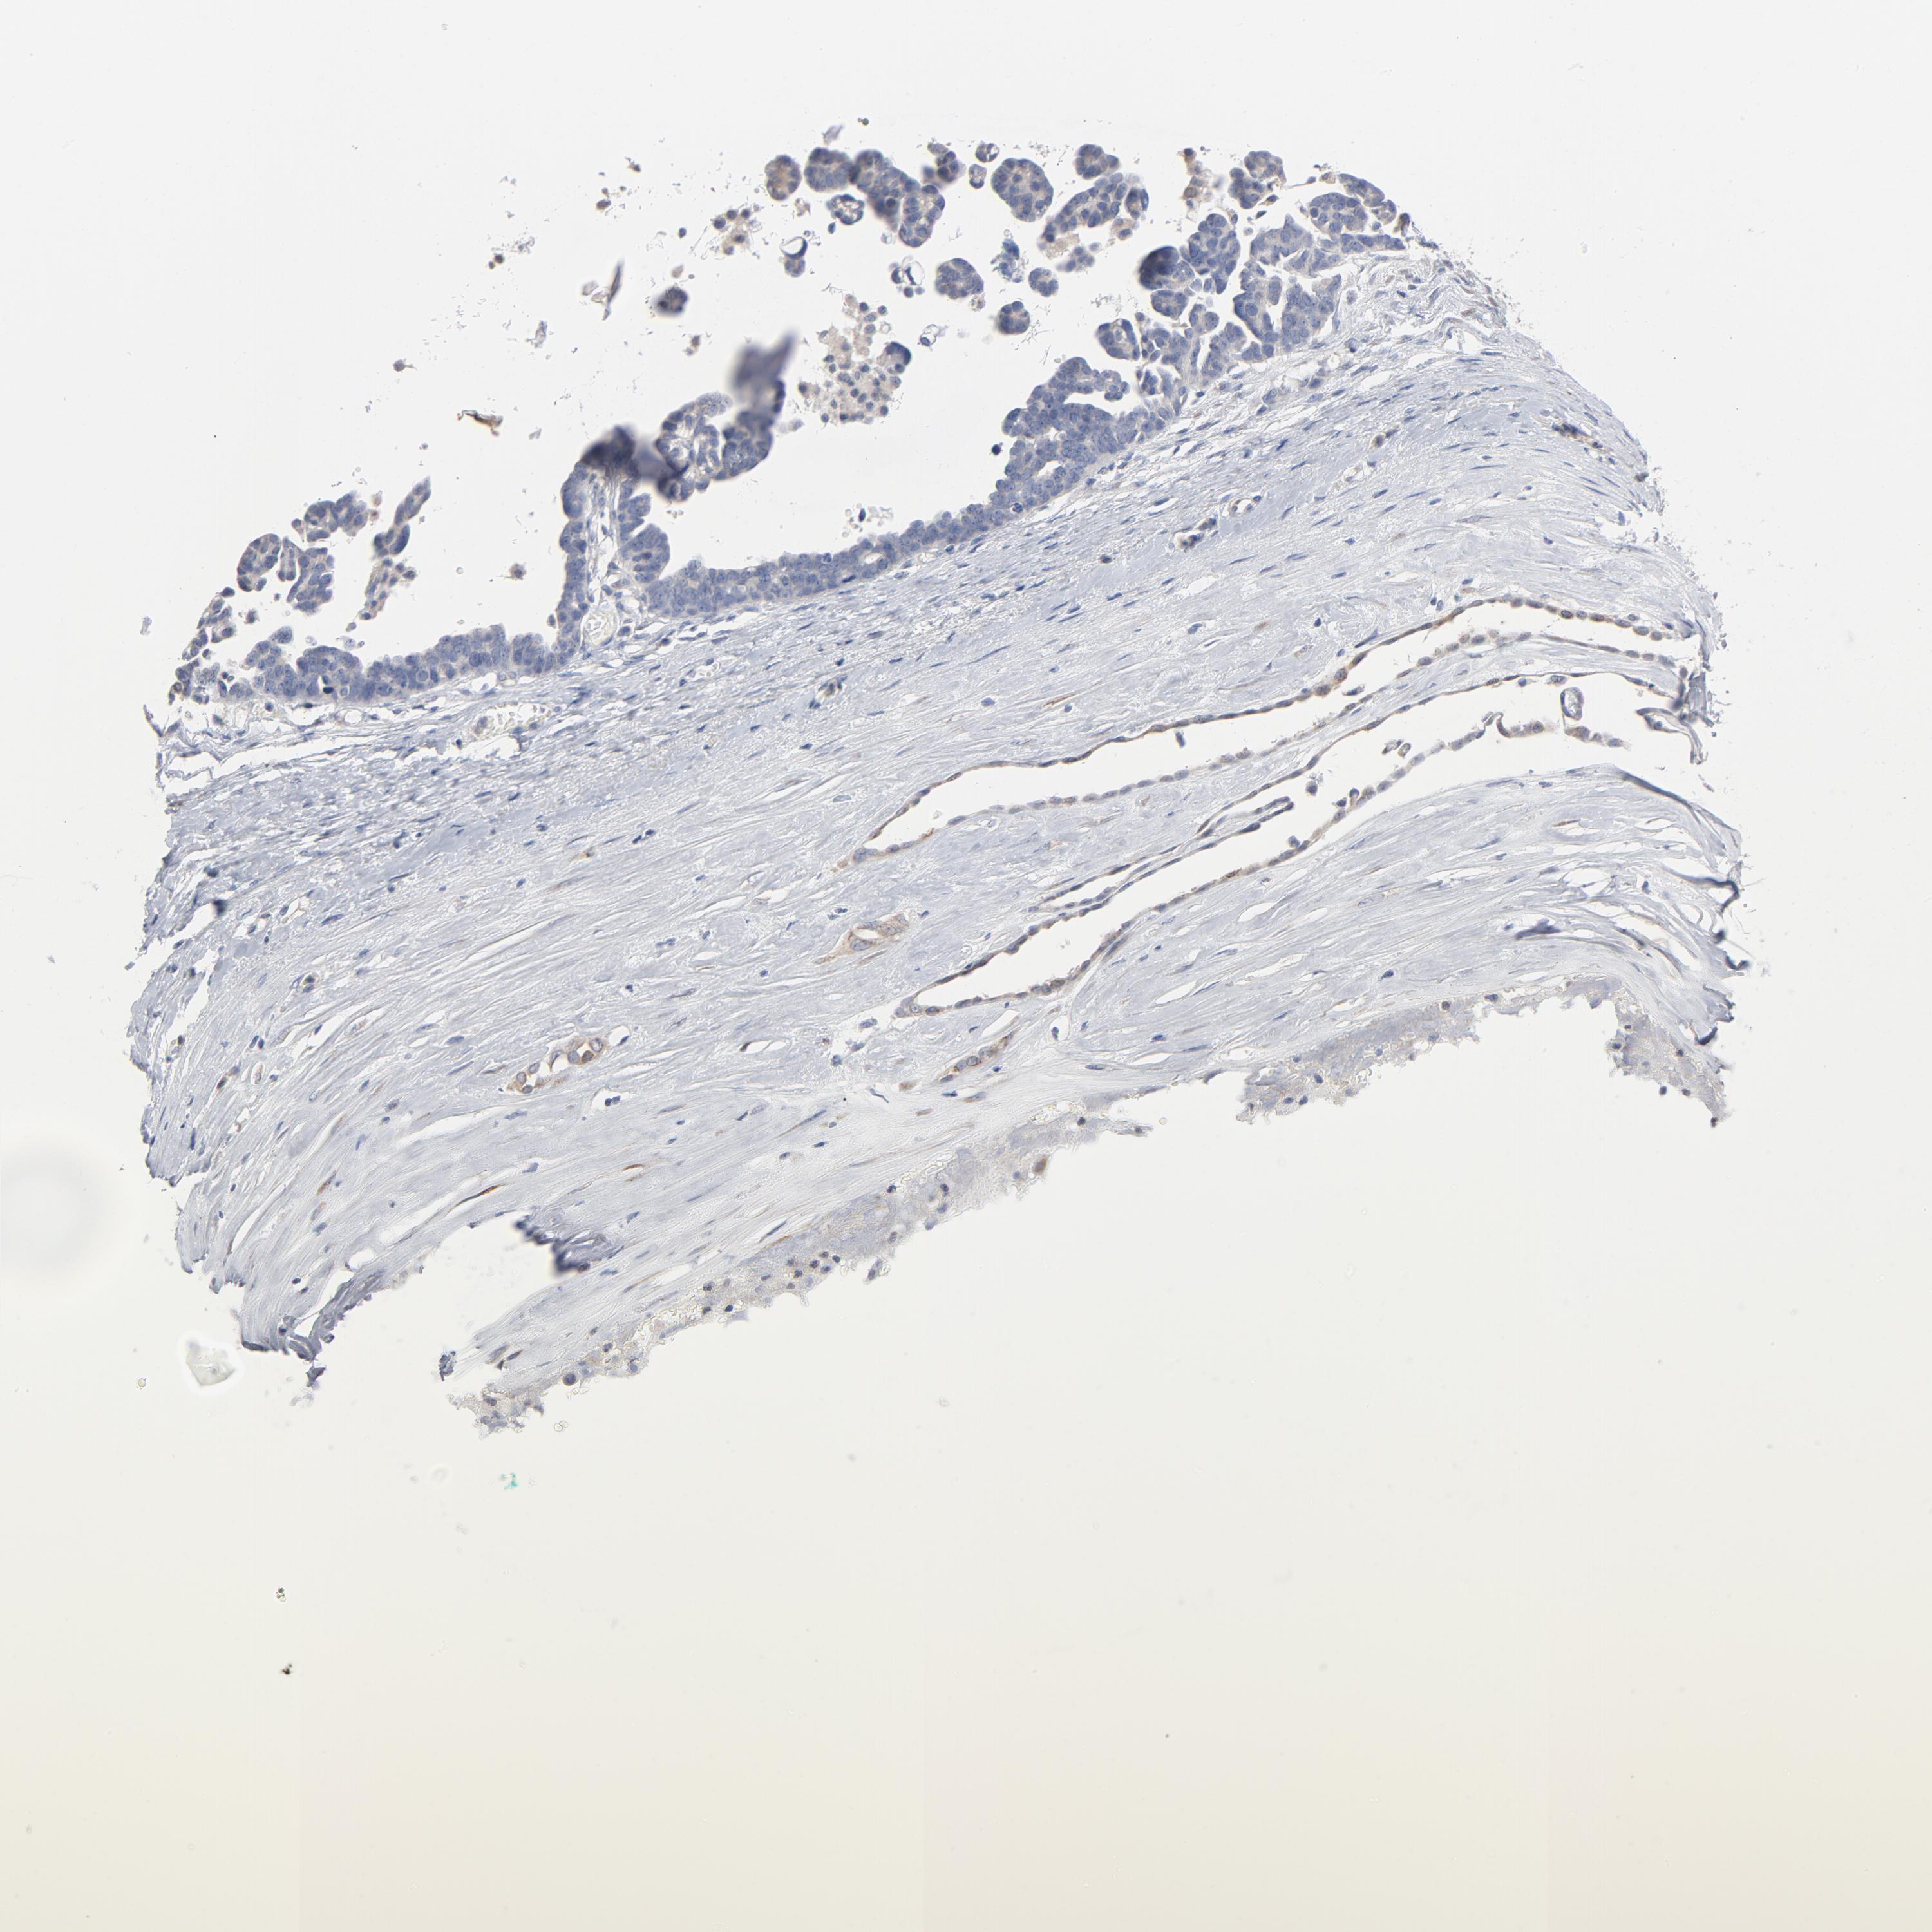

OVARIAN CANCER - Protein expressioni

A mouse-over function shows sample information and annotation data. Click on an image to view it in a full screen mode. Samples can be filtered based on level of antibody staining by selecting one or several of the following categories: high, medium, low and not detected. The assay and annotation is described here.

Note that samples used for immunohistochemistry by the Human Protein Atlas do not correspond to samples in the TCGA dataset.

Antibody stainingi

Antibody staining in the annotated cell types in the current human tissue is reported as not detected, low, medium, or high, based on conventional immunohistochemistry profiling in selected tissues. This score is based on the combination of the staining intensity and fraction of stained cells.

Each image is clickable and will lead to virtual microscopy that enables deeper exploration of all samples and also displays staining intensity scores, fraction scores and subcellular localization as well as patient and tissue information for each sample.

Antibody HPA003543

Staining

High

Medium

Low

Not detected

Intensity

Strong

Moderate

Weak

Negative

Quantity

>75%

75%-25%

<25%

None

Location

Nuclear

Cytoplasmic/membranous

Cytoplasmic/membranous,nuclear

Cystadenocarcinoma, serous, NOS

Cystadenocarcinoma, mucinous, NOS

Carcinoma, endometroid